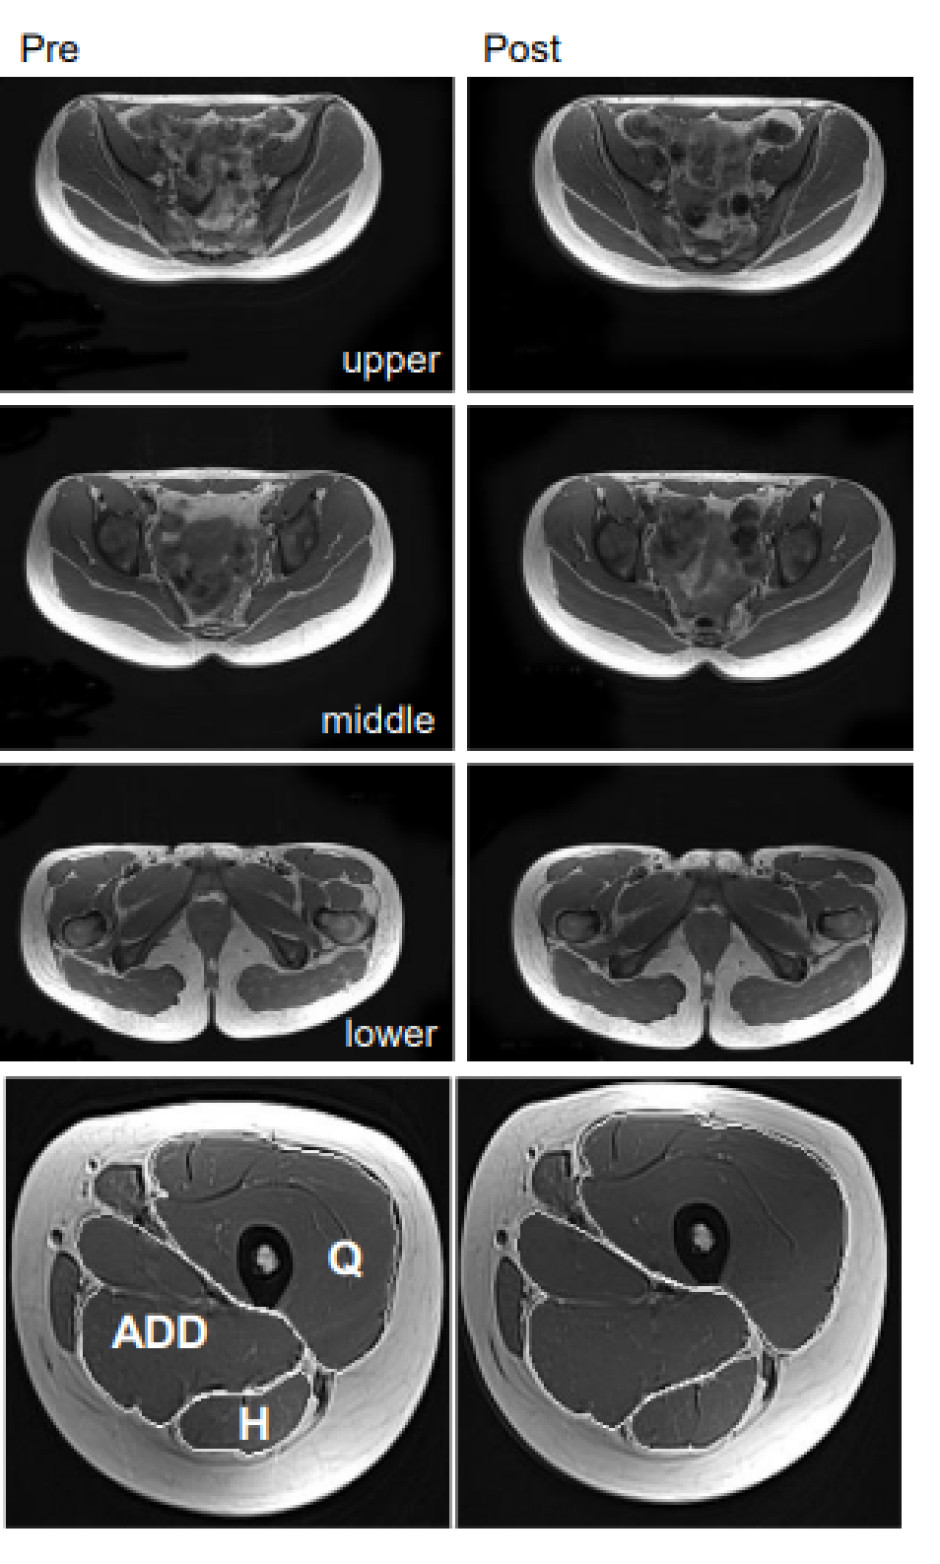

Muskelvekst ble målt som muskeltverrsnitt for øvre, midtre, og nedre del av gluteus maximus. I tillegg ble tverrsnitt målt og rapportert for quadriceps, adduktor-gruppen, og hamstring som vist på figur 1.

Figur 1. Viser hvordan muskelvekst ble målt i pre- og post-test. Tre øverste bilder viser tverrsnitt av øvre, midtre, og nedre del av gluteus maximus. Nederste bilde viser tverrsnitt av hele quadriceps, adduktor-gruppen og hamstring.